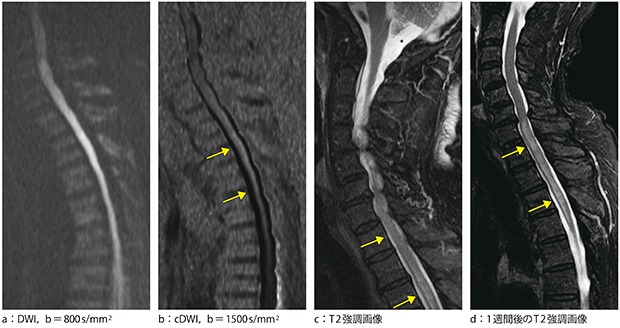

3.脊髄サルコイドーシス(疑い)

症例は80歳代,男性。脊髄は空気の影響を受けるため,通常のb=800s/mm2のDWI(図4 a)では脊髄全体の信号が上昇してしまい病変を認識しにくい。

本例では,b=1500s/mm2のcDWI(図4 b)で病変部の認識が可能となった。T2強調画像(図4 c)では,淡く高信号があるように見える程度の所見である。1週間後のT2強調画像(図4 d)で病変が増悪したため,他院へ紹介となった。

図4 脊髄サルコイドーシス(疑い)症例